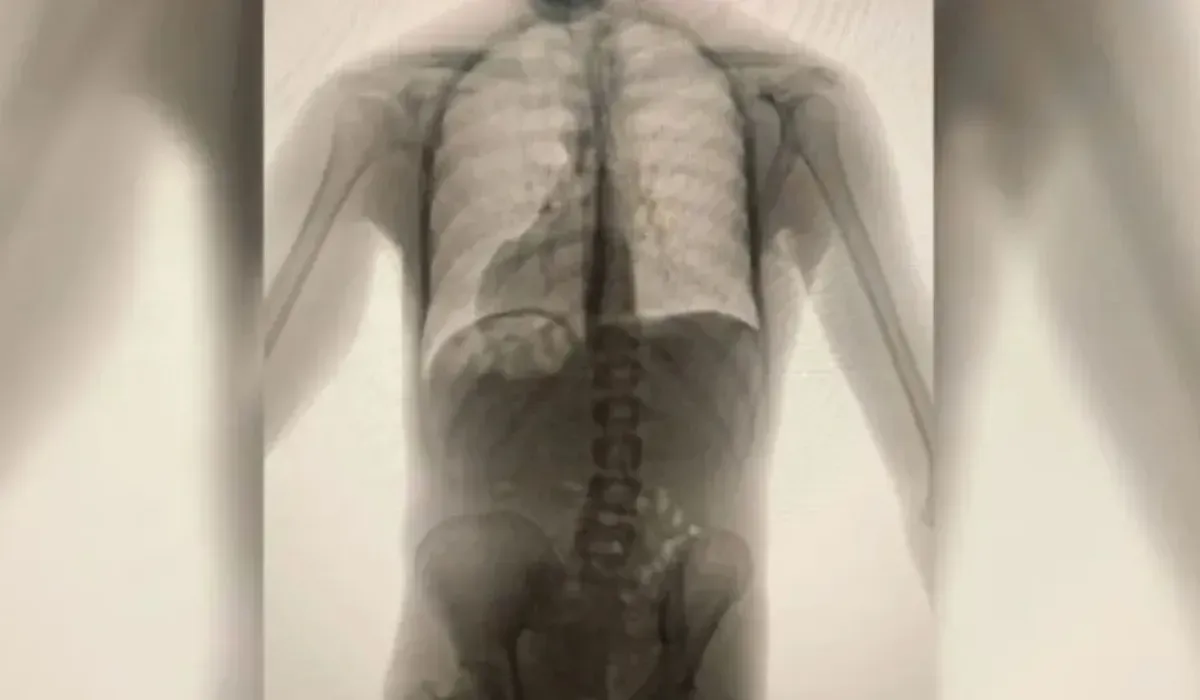

En el nosocomio cabecera de la provincia, tras los exámenes realizados, el preso fue diagnosticado por "consumo de estupefacientes", observándose cuerpos extraños en su estómago, constatándose luego que el protagonista había ingerido 180 cápsulas de marihuana, seguramente con el fin de distribuirlas dentro de la cárcel.